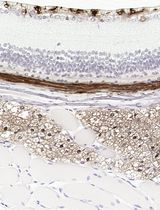

Figure 1. Pictures of a rosette taken 15s apart, Giemsa stained-wet mount method. Under wet mount condition, the cells are mobile, which helps to differentiate between rosettes and mere overlaps of cells. The Giemsa stain assists in visualizing the parasites. Scale bars: 10 µm.